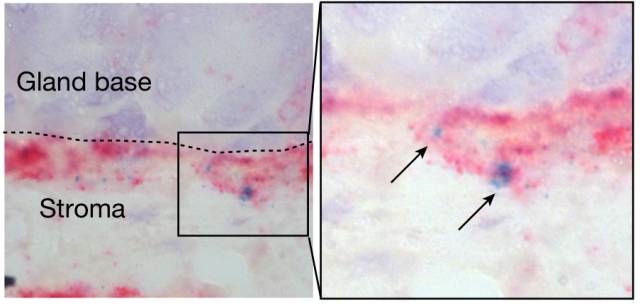

ن¹‹ه‰چ�,�,�,�,马ه…‹و–¯و™®وœ—ه…‹çڑ„ن¸´ه؛ٹه¦ه®¶Michael Sigalه°±ه·²ç»ڈهڈ‘وکژ�,�,�,�,ه¹½é—¨è؛و†èڈŒن¸چن½†ن»…هڈھن¼ڑç†ڈوں“胃ç²ک膜ه¤–貌çڑ„细èƒ�,�,�,�,ه¹¶ن¸”è؟کن¼ڑن¾µه…¥هˆ°èƒƒç²ک膜و·±éƒ¨�,�,�,�,وٹµè¾¾ه¹²ç»†èƒو± م€‚�م€‚م€‚هگŒو—¶�,�,�,�,Sigalè؟ک视ه¯ںهˆ°�,�,�,�,è؟™ن؛›ه¹²ç»†èƒè؟کن¼ڑé€ڑè؟‡ه¢و·»ه…¶ç ´ç¢ژو¥ه¯¹ç†ڈوں“هپڑه‡؛هڈچه؛”(8)م€‚�م€‚م€‚وک¯ن¸چوک¯è؟™ن¸ھهژ†ç¨‹ه¯¼è‡´ن؛†èƒƒç™Œï¼ںï¼ں那详细وœ؛هˆ¶هڈˆوک¯ن»€ن¹ˆه‘¢ï¼ںï¼ں

ه¹²ç»†èƒن½چن؛ژ胃è…؛çڑ„ه؛•éƒ¨�,�,�,�,هڈ—هں؛è´¨وˆگç؛¤ç»´ç»†èƒé‡ٹو”¾çڑ„R-è„ٹé«“هچµç™½هچµç™½ï¼ˆç®ه¤´ï¼‰è°ƒçگ†ه¢و®–و´»و€§

ه·²وœ‰ç ”究و‰¹و³¨�,�,�,�,هœ¨و£ه¸¸ه¹²ç»†èƒه¢و®–هژ†ç¨‹ن¸�,�,�,�,DNAه¤چهˆ¶هژ†ç¨‹ن¸çˆ†هڈ‘çڑ„éڑڈوœ؛çھپهڈکوک¯ن¸€ç§چه¼؛烈çڑ„致癌ه› ç´ �,�,�,�,ه‡Œé©¾éپ—ن¼ ن»¥هڈٹوƒ…ه½¢ه› ç´ ç‰ï¼ˆ9)م€‚�م€‚م€‚ه› و¤�,�,�,�,ه¹½é—¨è؛و†èڈŒه¾ˆوœ‰هڈ¯èƒ½وک¯é€ڑè؟‡ه¢è؟›èƒƒç²ک膜ه¹²ç»†èƒçڑ„ه¤ھè؟‡ه¢و®–�,�,�,�,ه¼•èµ·ه¤§ه®—DNAوچںن¼¤�,�,�,�,وœ€ç»ˆè¯±ه¯¼èƒƒç™Œçڑ„爆هڈ‘م€‚�م€‚م€‚

ن¸؛ن؛†ç،®ه®ڑه¹½é—¨è؛و†èڈŒè¯¦ç»†وک¯و€ژو ·ه¢è؟›èƒƒç²ک膜ه¹²ç»†èƒه¢و®–çڑ„م€‚�م€‚م€‚Meyerهچڑه£«وژ¥ç؛³هچ•هˆ†هگهژںن½چو‚ن؛¤و‰‹è‰؛ه¯¹ه°ڈé¼ èƒƒç²ک膜ه¹²ç»†èƒن¸¾è،Œç³»ç»ںه‰–وگم€‚�م€‚م€‚و•ˆوœهڈ‘وکژ�,�,�,�,ه°ڈé¼ çڑ„胃ç²ک膜ن¸‹�,�,�,�,ن½چن؛ژ胃è…؛هں؛ه؛•çڑ„ه¹²ç»†èƒو± ن¸ن؟هکن¸¤ç§چه·®هˆ«ç±»ه‹çڑ„ه¹²ç»†èƒم€‚�م€‚م€‚ن¸€ç§چه¹²ç»†èƒهˆ†è§£و°´ه¹³ن½ژ�,�,�,�,ه¢و®–能هٹ›ه¼؛�,�,�,�,هڈ¦ن¸€ç§چهˆ†è§£و°´ه¹³è¾ƒé«ک�,�,�,�,ه¢و®–能هٹ›è¾ƒه¼±م€‚�م€‚م€‚

هگŒو—¶�,�,�,�,Meyerهچڑه£«è؟کهڈ‘وکژ�,�,�,�,ه½“ه¹½é—¨è؛و†èڈŒن¾µه…¥و—¶�,�,�,�,胃ç²ک膜ن¸‹و–¹çڑ„é—´è´¨وˆگç؛¤ç»´ç»†èƒن¼ڑو¸—é€ڈن¸€ç§چهگچن¸؛R-è„ٹé«“هچµç™½ï¼ˆRspo)çڑ„物质�,�,�,�,ن½œç”¨ن؛ژ胃ç²ک膜ن¸‹و–¹ه¹²ç»†èƒو± �,�,�,�,و؟€و´»ه¹²ç»†èƒçڑ„WNTé€ڑ路调çگ†ه¹²ç»†èƒçڑ„ه¢و®–ن»¥ه؛”ه¯¹ه¹½é—¨è؛و†èڈŒç†ڈوں“م€‚�م€‚م€‚